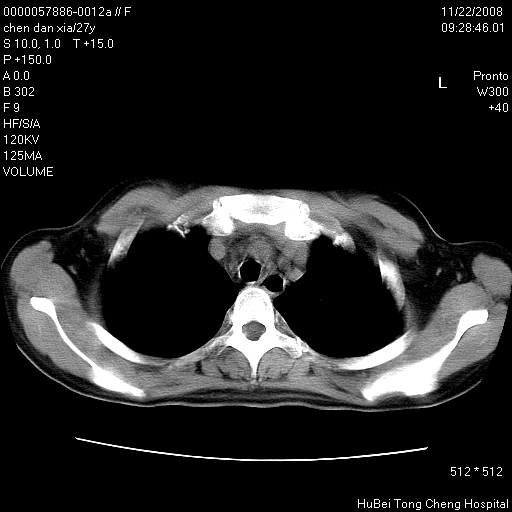

标题: CT16752:F,27Y。发热咳嗽20余天,伴盗汗。 [打印本页]

标题: CT16752:F,27Y。发热咳嗽20余天,伴盗汗。

气管前腔静脉后淋巴结肿大 右肺门纹理模糊

淋巴结核?

右下肺纹理模糊;纵隔可见肿大淋巴节;右心缘旁结节,边缘光滑,纵隔窗病变范围较肺窗明显小,首先考虑右下肺结核,不排外淋巴瘤

下肺结节,结节内钙化,肺门纵隔淋巴肿大 结核可能性大

气管前腔静脉后淋巴结肿大 右肺门纹理模糊[br]淋巴结核?